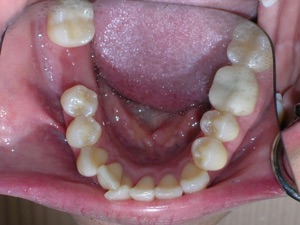

Here’s an example from a woman who had very significant crowding. There was a missing tooth on the bottom right. We considered extracting three other teeth, but decided not to.

Instead we decided to do braces and treat on a non extraction basis with trimming or shaving between teeth to create additional space.

We placed braces and begun a process of trimming or narrowing select teeth. Note that it is a painless procedure, and no anesthesia was needed.